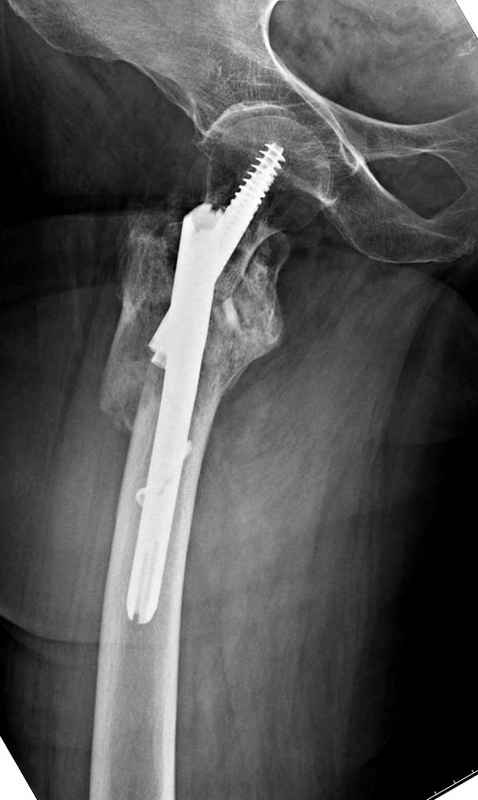

Из фиксаторов, мы бы применили цефаломедуллярные, потому что они "по закону моментов" из-за короткого рычага от центра головки к диафизу и по принципу "головка диафиз" механически лучше выдерживают нагрузки, чем пластины.

Но современные пластины с угловой стабильностью не отстают от медуллярных конструкций. Межфрагментарные шурупы и имплант как нейтрализирующее создаст адекватную фиксацию.

Здесь пара случаев фиксации похожих переломов:

первый высокоэнергетическая травма 36 лет

Здесь 83 года, травма в результате падения